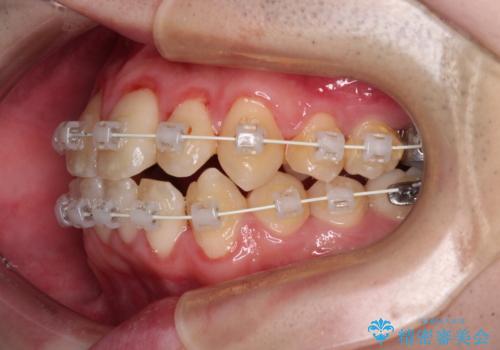

- 審美装置

- 2年1ヶ月

シザーズバイトは強く咬合する奥歯を移動させるため、多くの場合においてワイヤー矯正の装置のみでは改善が困難となります。

奥歯の咬み合わせ改善は治療初期からしっかりとアプローチする必要があるため、補助装置を積極的に利用します。